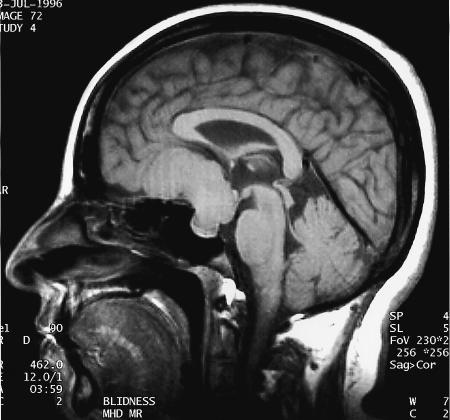

腦膜瘤生長(zhǎng)緩慢,常壓迫周圍組織引起相應(yīng)的神經(jīng)癥狀和體征,造成不同的障礙與腫瘤部位有關(guān)。腦膜瘤的典型CT表現(xiàn)是什么?腦膜瘤MRI表現(xiàn)有哪些?...

臨床醫(yī)學(xué)材料 病人女58歲,因頭疼30年,左眼眼睛視力下降3個(gè)月就醫(yī),病人30年以前無(wú)發(fā)病原因發(fā)生頭疼,無(wú)其它病癥,未引起重視,3個(gè)月前,病人主動(dòng)眼...